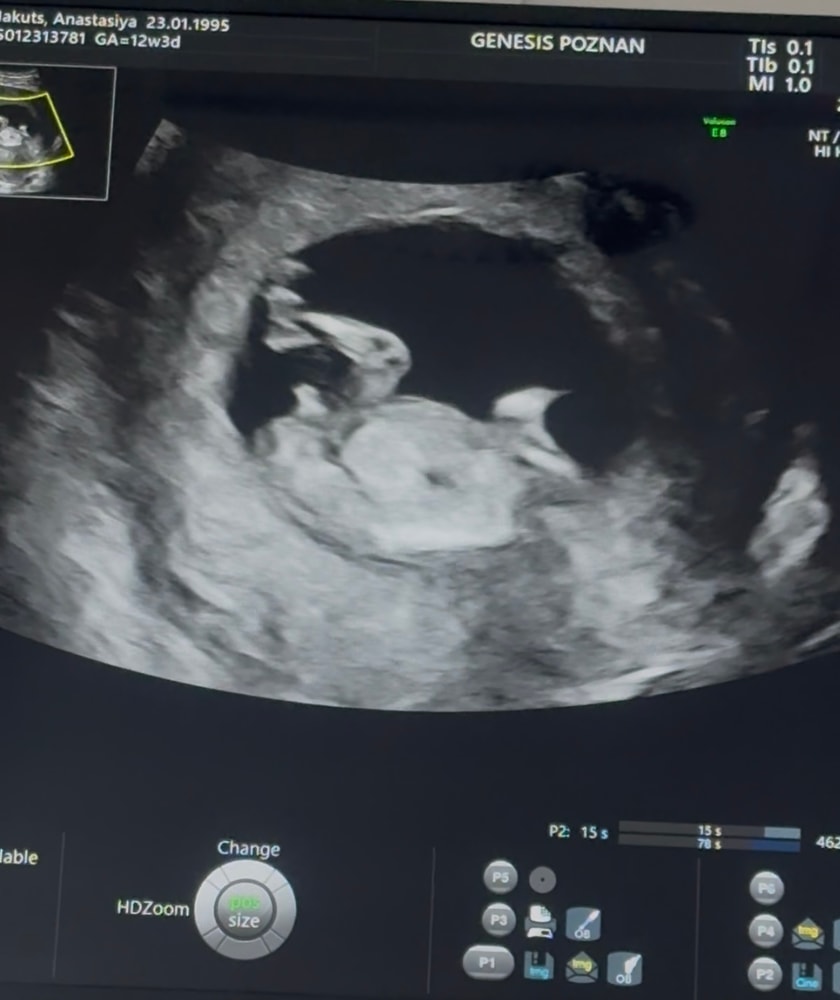

Определение пола☺️

РАЗНОЕ (если тема больше не подходит ни к одной категории, пишем сюда)Девочки, нужно ваше экспертное мнение. Была на первом скрининге, про пол почему-то не спросила. Понимаю, что это ещё рано и стопроцентной уверенности быть не может, но всё же интересно предположить 😅

А вы как думаете, кто у нас? И вообще, это тот самый «бугорок»?

Тут вроде очевидно)) мальчишка

Как мне врач УЗИ сказала на скрининга: какой нескромный мальчик! Всё на показ))